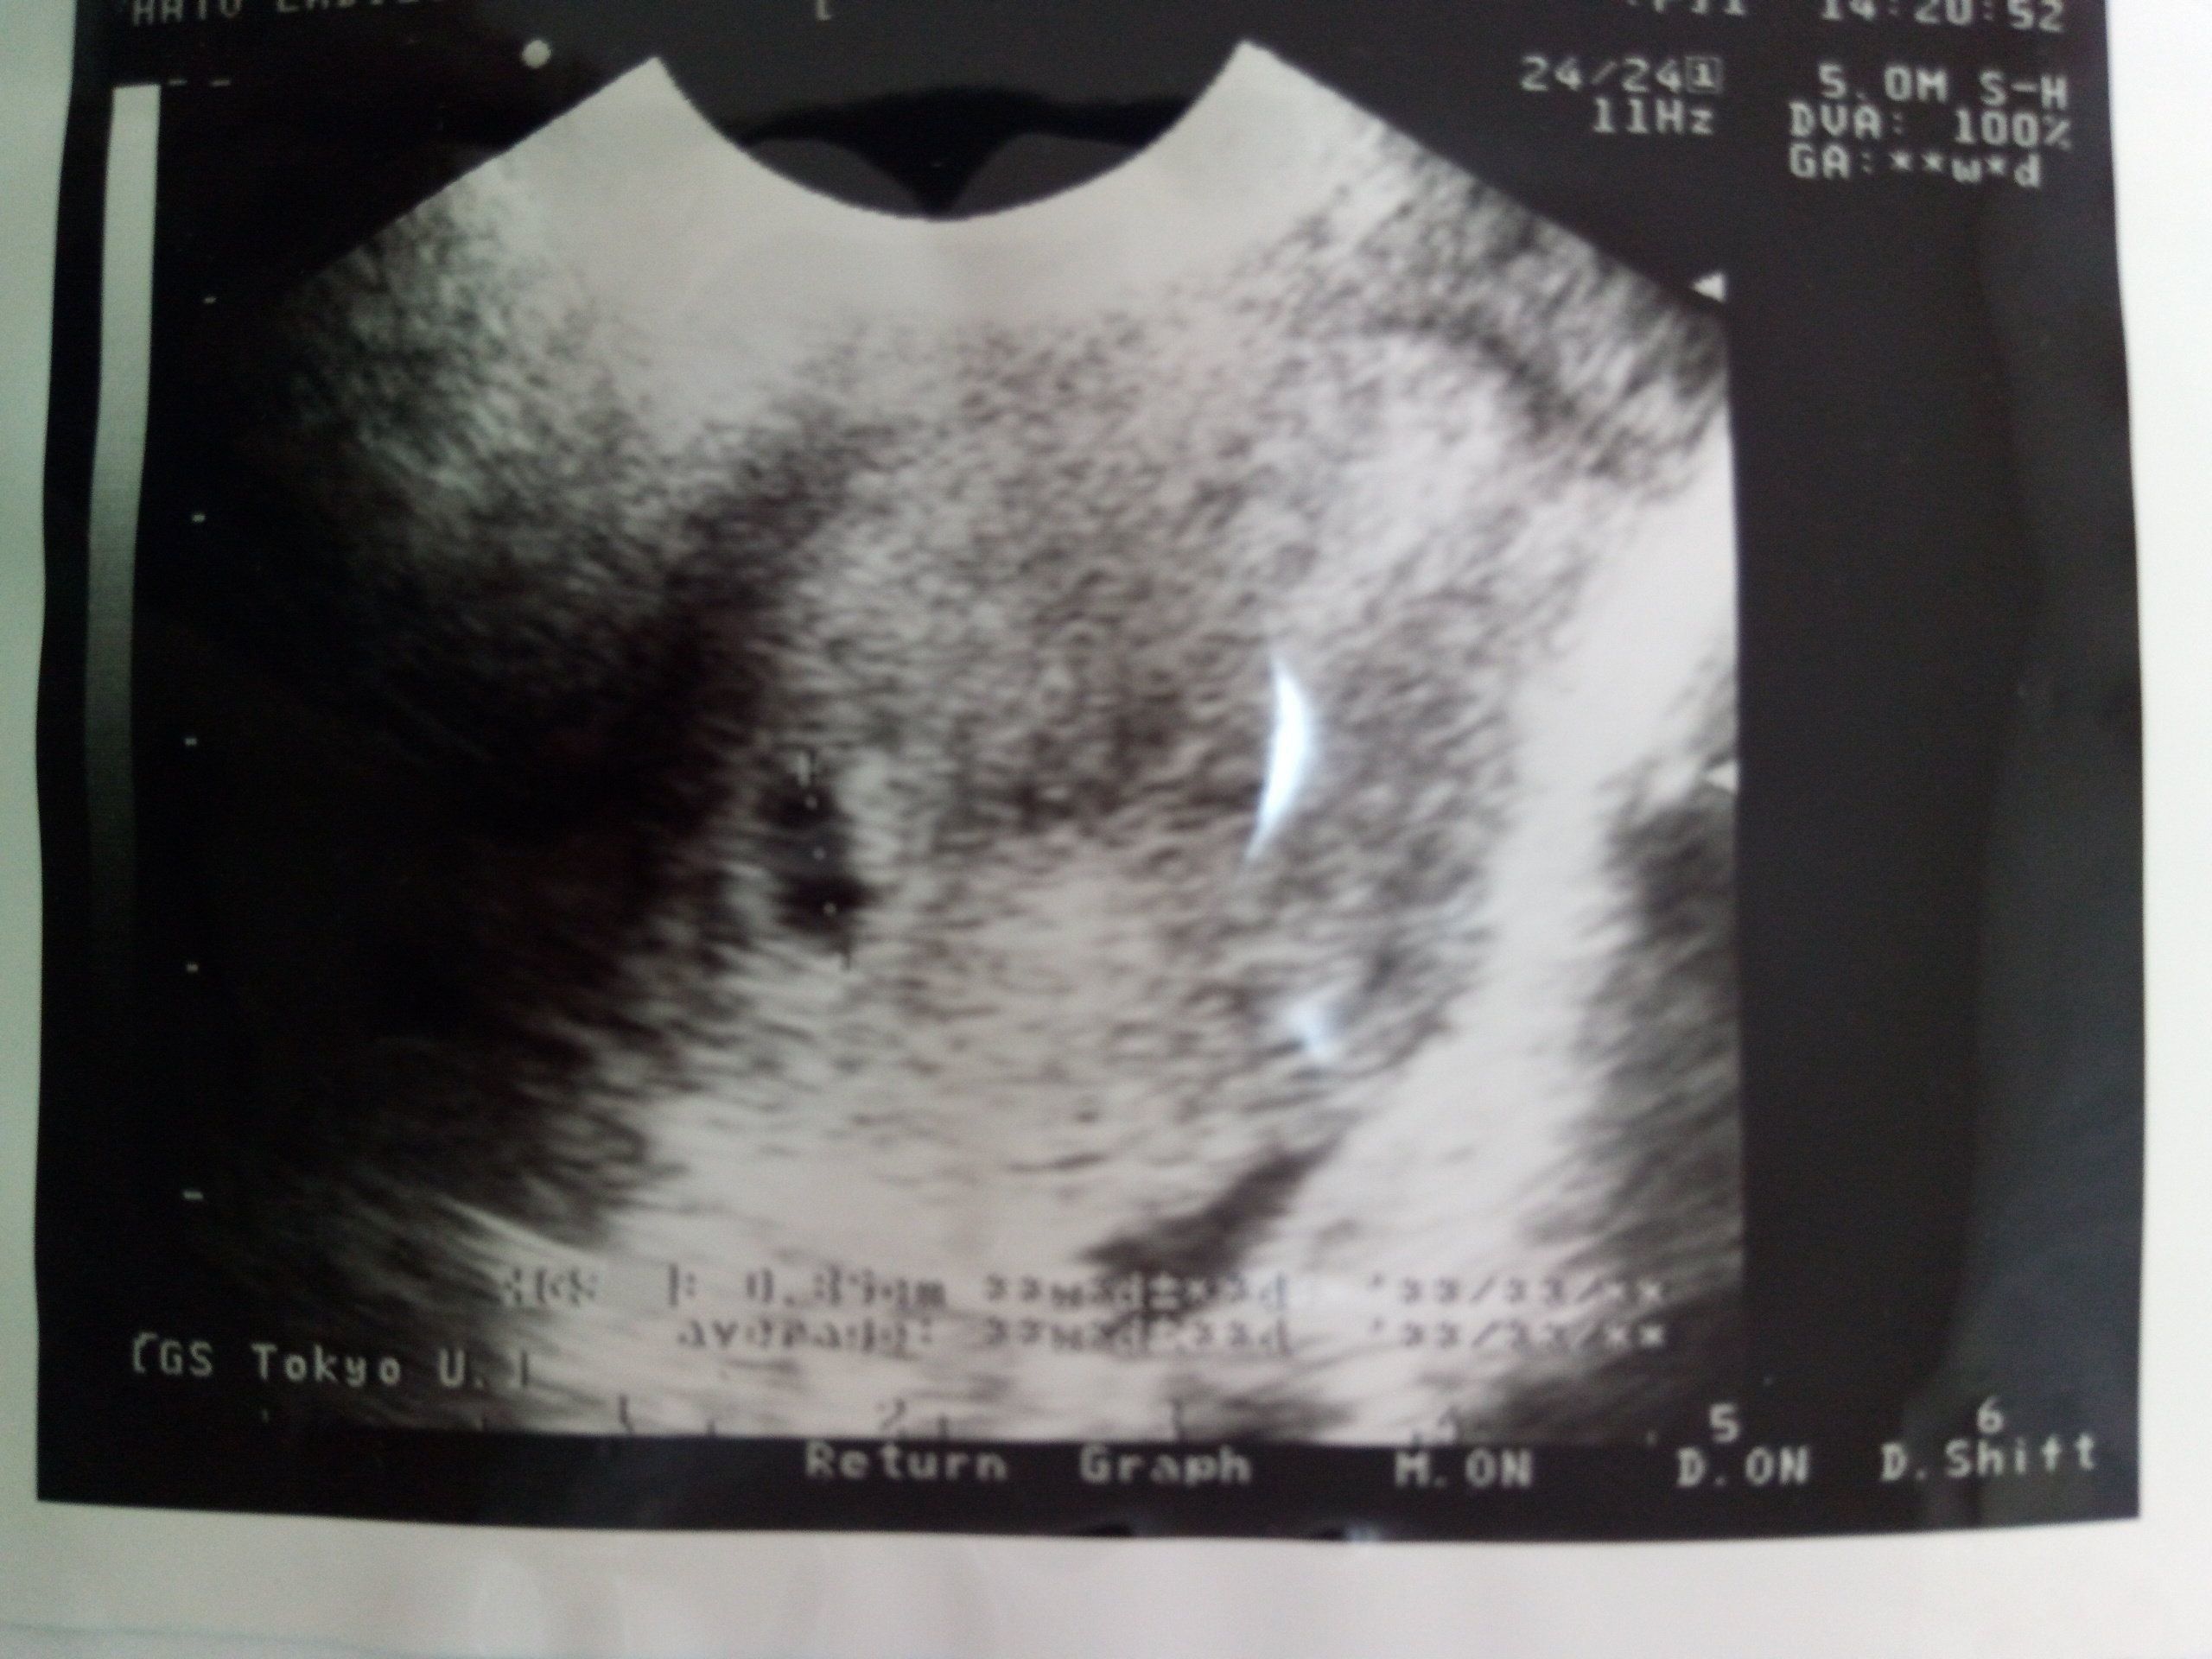

妊娠36週のエコー写真 存在感あるなあ!出産へのカウントダウン始まる

臨月に入って、いよいよ毎週の通院になりました。赤ちゃんが出産に向けて元気であるかどうか調べるNST(ノンストレステスト)も始まり、出産へのカウントダウンが始まりました。